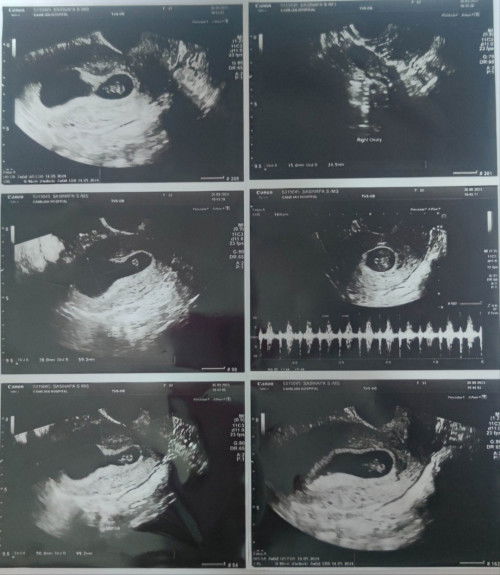

7Week+4Day ภาวะแท้งคุกคาม

ท้องที่2 หลังจากท้องแรกแท้งไป ด้วยอายุครรภ์ที่น้อยมากๆ พอมาท้องนี้ ทำให้เราต้องสังเกตุอาการทุกอย่าง เวลาเข้าห้องน้ำต้องคอยสังเกตุที่กระดาษชำระที่เราซับว่ามีสีอะไรแปลกปลอมติดออกมาไหม แล้วมันก็เกิดขึ้นจริงๆ เราพบคราบเลือดออกสีน้ำตาล ซึ่งเราก็ไม่นิ่งนอนใจ ไปพบแพทย์ทันทีในวันนั้น หมอทำตรวจภายในอันดดับแรก พบมีเลือดออกจริง จึงวินิจฉัยว่า มีภาวะแท้งคุกคาม และ ได้ทำการอัลตร้าซาวน์ พบว่าน้องยังอยู่ดี น้องอยู๋ในมดลูก และ อยู่ในตำแหน่งที่ดี เป็นครั้งแรกที่ได้ยินเสียงหัวใจลูก สรุปหมอทำการรักษา โดยฉีดยากันแท้ง โดยต้องฉีดต่อเนื่องทุกWeek จนกว่าจะครบ 10Week (คำพูดทางการแพทย์ การฉีดยากันแท้ง ไม่ได้หมายความว่าคุณจะไม่แท้ง) และ ให้วิตามินกลับมากกิน แต่ไม่ได้ห้ามให้เดินทางหรือทำอะไรยังไม่ถึงกับขั้นนอนเฉยๆบนเตียง อยากให้แม่ๆคอยสังเกตุตัวเอง คำว่าเลือดล้างหน้าเด็กทางการแพทย์ไม่มีคำนี้ค่ะ มีแต่คำว่า คนท้องไม่ควรมีเลือดออก ตอนนี้เราได้แต่ภาวะนา และ ดูแลตัวเอง ขอให้น้องไม่เป็นอะไรค่ะ ไว้จะมาอัปเดตให้ทราบนะคะ เผื่อเป็นประสบการณ์ให้กับแม่ๆท่านอื่น